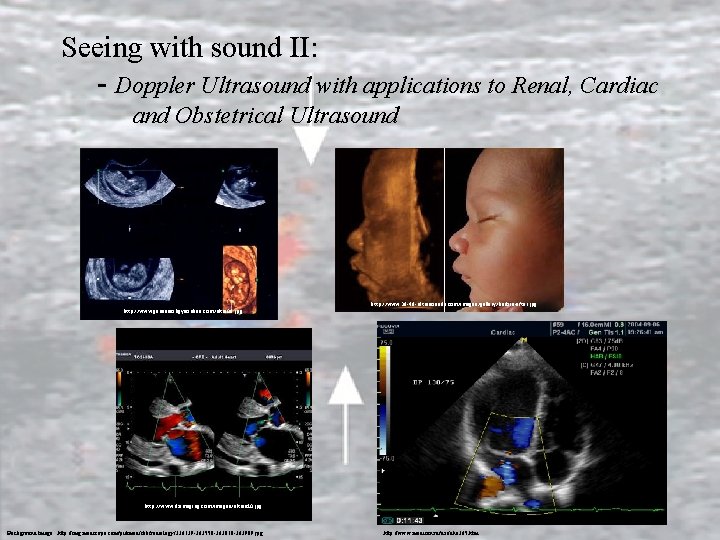

Seeing with sound II: - Doppler Ultrasound with applications to Renal, Cardiac and Obstetrical Ultrasound http: //www. genesisobgynonline. com/ultra 08. jpg http: //www. 3 d-4 d-ultrasounds. com/images/gallery/before-after. jpg http: //www. dximaging. com/images/ultras 10. jpg Background Image: http: //img. medscape. com/pi/emed/ckb/radiology/336139 -363550 -363818 -363989. jpg http: //www. medison. ru/uzi/eho 365. htm